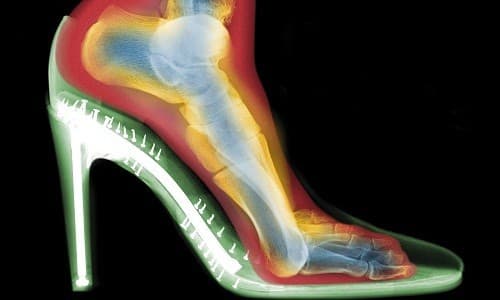

Phụ nữ thường mang giày cao gót khi đi chơi, đi dancing hay đi làm. Tuy nhiên thường xuyên đi giày cao gót là nguyên nhân gây đau khớp chân. Xét về mặt lịch sử, việc đi trên đôi chân của mình là kết quả của quá trình tiến hóa để tạo thành con người, khi mà với dáng đứng thẳng, hai chi trước có thể giải phóng và trở thành công cụ làm việc. Tuy nhiên, chính dáng đứng thẳng cũng là một nguy cơ đối với các khớp chi dưới và cột sống khi các cấu trúc này phải hứng chịu trọng lượng của chính cơ thể. Ngoài ra khi lao động, mang vác vật nặng thì cơ thể lại phải chịu những tải trọng bổ sung, dễ dẫn đến tổn thương cơ xương khớp. Nhưng cơ thể lại có những cơ cấu thích nghi với điều kiện mới. Bàn chân có cấu trúc vòm khiến trọng lượng cơ thể được phân bố đều trên cả diện tích bàn chân. Tuy nhiên khi dùng giày cao gót, cơ chế vòm của bàn chân bị phá vỡ.

Giày cao gót thường có sự chênh lệch đáng kể độ cao giữa đế giày và mũi giày. Khi đi giày cao gót thì gót chân ở vị trí cao hơn đáng kể so với mũi bàn chân, do vậy gót chân phải trực tiếp chịu sức nặng của cơ thể. Mô mềm gan bàn chân vốn có tác dụng như một giảm xóc cũng không chịu được tải trọng quá lớn, bị chấn thương kéo dài. Dần dần mọc gai xương gót, có thể làm tổn thương vùng gót chân bị tăng lên đáng kể.

Mũi bàn chân là một phần phải chịu lực thứ hai sau cổ chân, lại bị bó hẹp do mũi giày nhọn ở đầu. Phần mũi bàn chân, đến lượt mình cũng phải hứng chịu phần đáng kể trọng lượng cơ thể, dẫn đến tình trạng thoái hóa sớm các khớp bàn chân, ngón chân và biến dạng khớp, đặc biệt là ngón chân cái bị trẹo ra ngoài, còn các ngón chân khác cũng bị biến dạng, thoái hóa ở các mức độ khác nhau. Bàn chân sưng phù do máu dồn về đôi chân gây cảm giác đau đớn, khó chịu.

Như vậy đi giày cao gót có thể gây phù, đau và biến dạng bàn chân, lỏng lẻo khớp cổ chân hay khớp cổ chân bị thoái hóa sớm, mọc gai xương gót. Mức độ tổn thương đôi chân phụ thuộc vào loại giày cao gót cũng như thời gian đi giày. Việc thường xuyên đi giày cao gót hoặc đi giày cao gót trong thời gian quá dài là nguyên nhân chủ yếu gia tăng mức độ tổn thương đôi chân. Mức độ tổn thương còn phụ thuộc cả vào cách thức sử dụng giày. Khi đi trên đường mấp mô hay bước hụt thì người chủ giày cao gót dễ dàng mất thăng bằng, trọng tâm lệch khỏi chân đế, dẫn đến phản xạ uốn lượn người để giữ thăng bằng, tương tự như động tác của diễn viên xiếc đi trên dây. Điều đó làm tăng tải trọng đột ngột lên các khớp. Gân cơ, dây chằng khớp cũng phải làm việc hết sức vất vả. Điều đó đẩy nhanh quá trình chấn thương chi dưới.